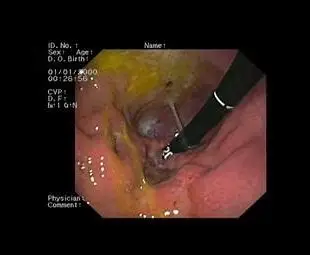

La fibroscopie digestive et respiratoire (y compris la rhinoscopie) ainsi que la cystoscopie sont des techniques de diagnostic et de traitement essentielles en médecine vétérinaire. Elles permettent d’explorer l’intérieur du corps de votre animal de manière non invasive, en utilisant des voies naturelles ou de très petites incisions. Ces procédures sont particulièrement utiles pour localiser et retirer des corps étrangers tels que des épillets coincés dans les voies respiratoires, digestives ou urinaires, ainsi que pour traiter des problèmes comme les calculs vésicaux.

Ces méthodes minimisent les traumatismes pour votre animal, réduisent les risques liés à des chirurgies plus invasives, et favorisent une récupération rapide. En utilisant ces techniques modernes, nous vous offrons des soins de haute qualité avec un maximum de confort pour votre compagnon.